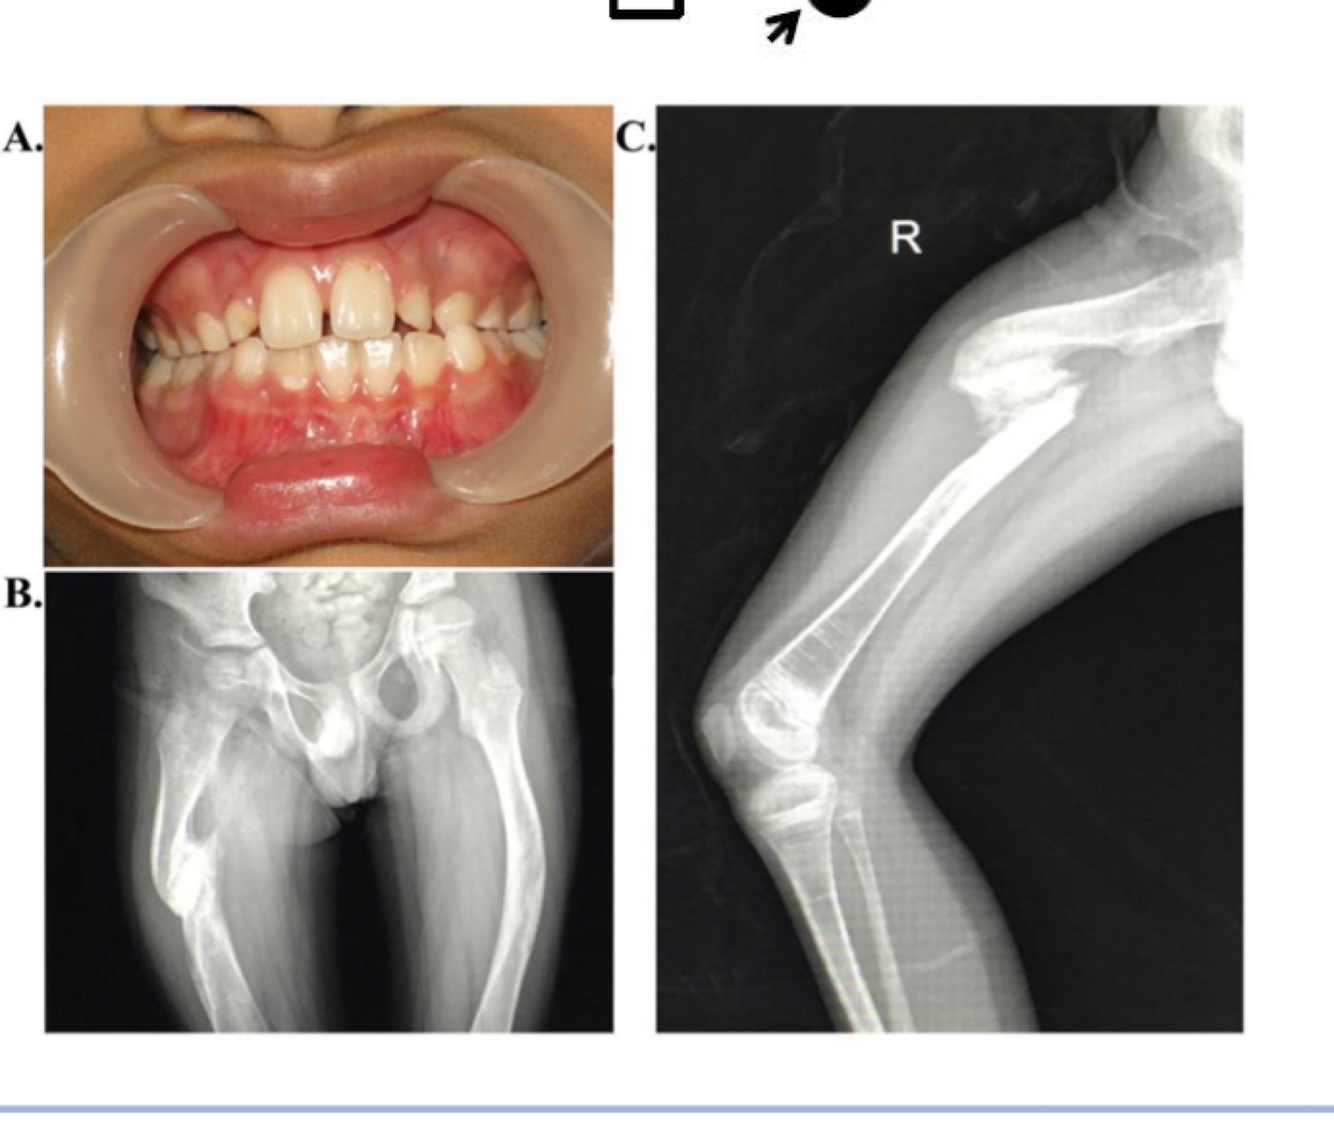

Clinical presentations of Duchenne Muscular dystrophy (DMD)

A

1) Progressive muscle weakness

2) Wheelchair dependency

3) delayed motor milestones

4) cardiomyopathy

Clnical case

• 3-year-old boy

• Unable to run

• Muscle weakness

• Uncle died at age 21 and was on wheelchair

• Muscle biopsy

• Loss-of-function mutations in the Dystrophin gene (X-linked recessive)

• Mostly deletions of part or all of the gene

Disorder?

DMD - Duchenne muscular Dystrophy